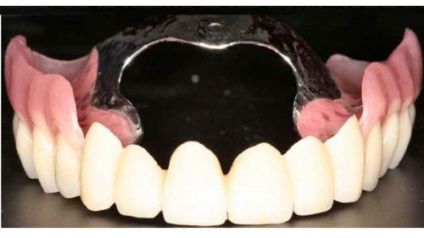

- Protezele. Construcția este montată pe maxilarului superior și inferior, prin intermediul agrafe sau un tampon special. Atunci când boala parodontala este folosit tehnologia specială pentru producerea de proteze, care minimizează impactul asupra mucoasei inflamate.

proteză dentară detașabil, în absența